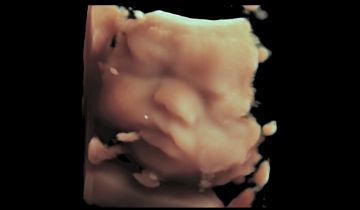

Siêu âm thai 4D có thể tạo ra hiệu ứng và hình ảnh rõ nét hơn tương tự như xem video trực tiếp. Sử dụng công nghệ này, ...